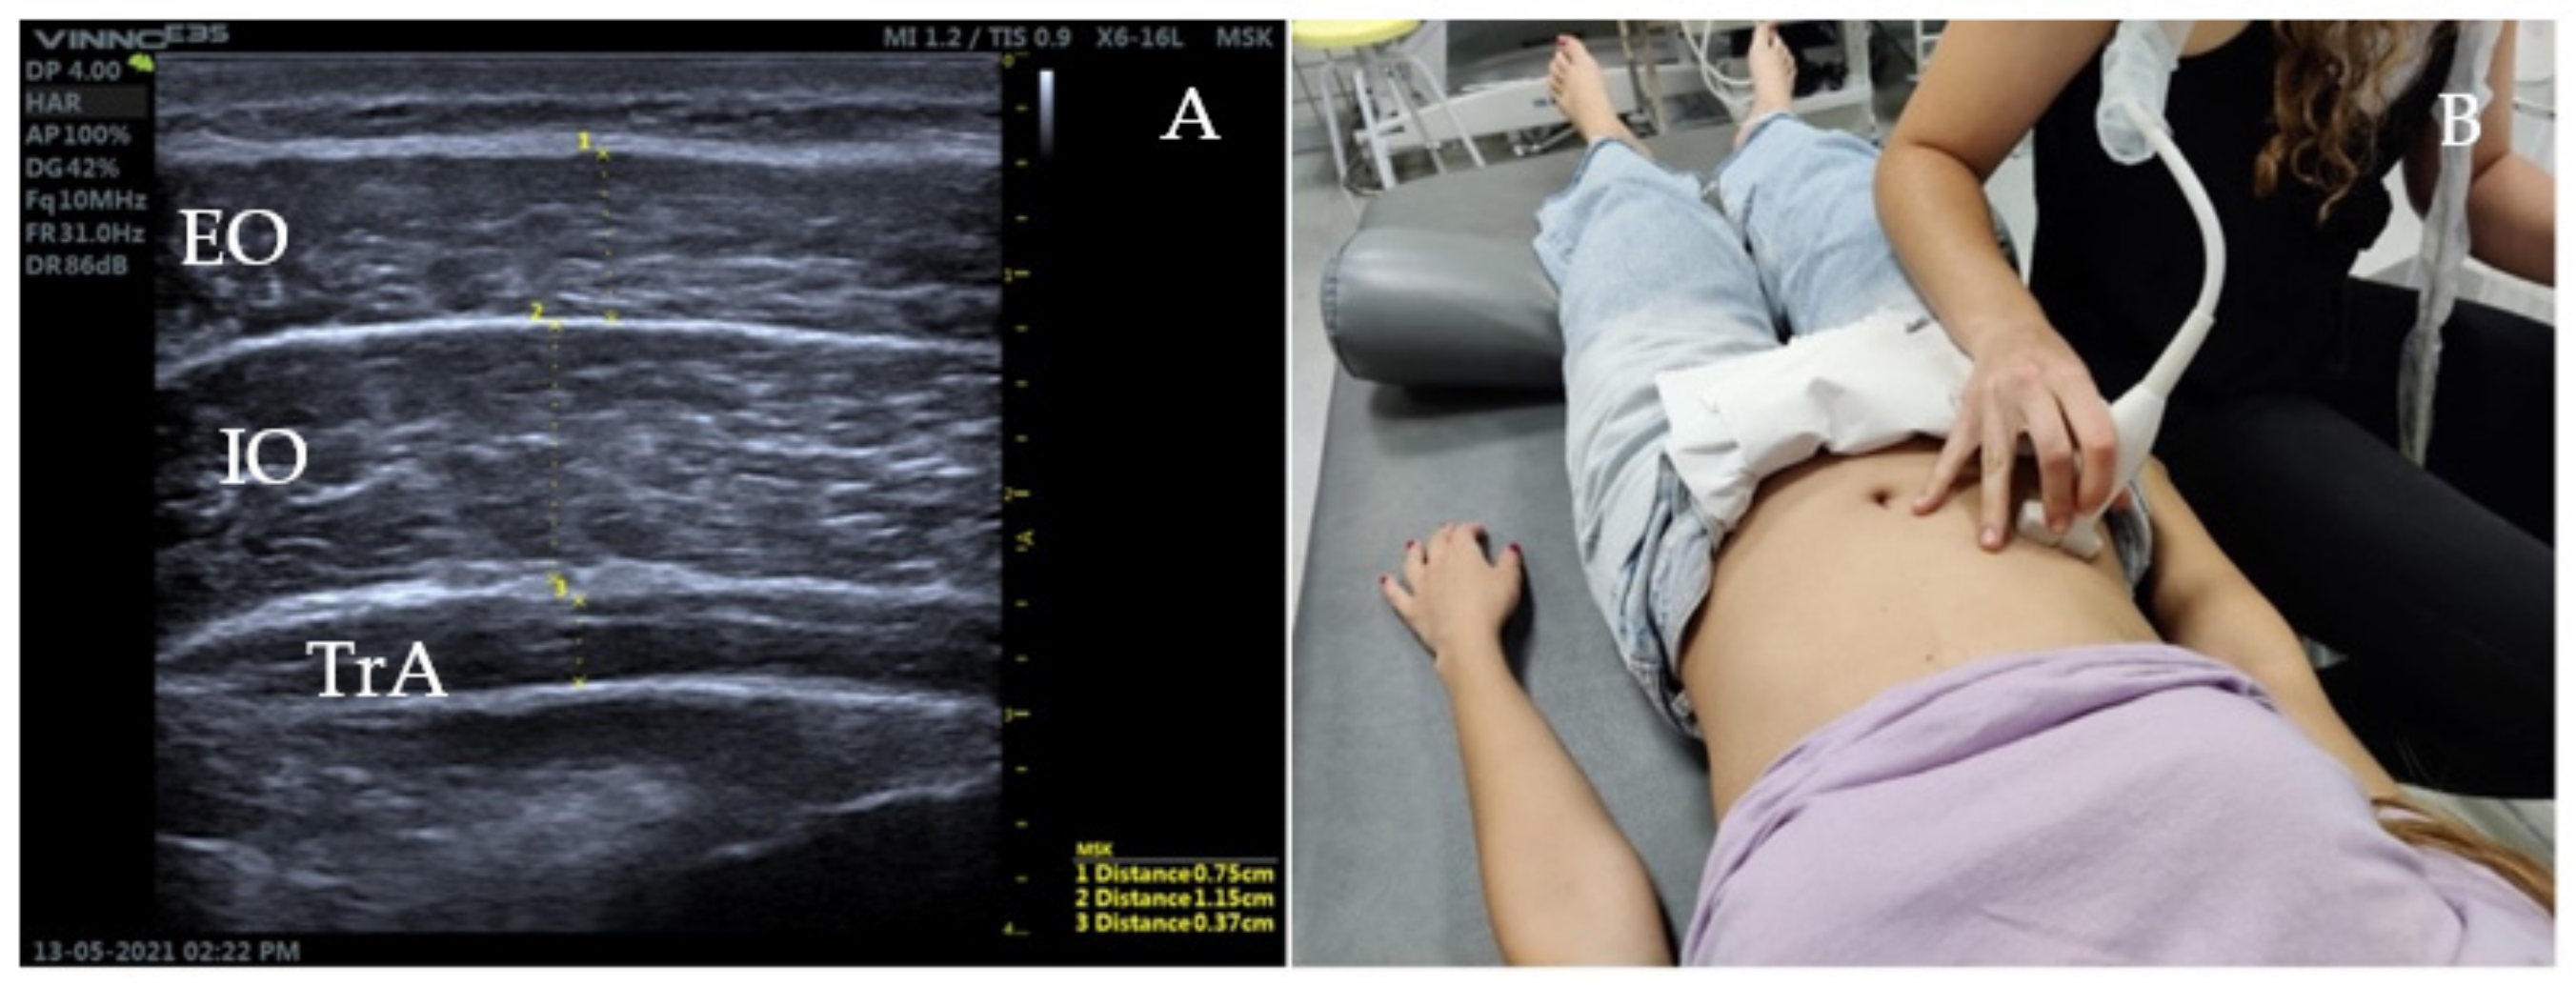

The patient will be positioned in supine position on the stretcher, in a relaxed position, with the hips flexed 45° and knees resting on a pillow [18]. A linear transducer with frequencies in the range 5–10 MHz will be used for greater accuracy [19]. To assess the lateral musculature (EO, IO, TA), the transducer will be oriented transversally to the longitudinal axis of the patient, in the medial abdominal region, between the costal cartilage of the eleventh rib and the iliac crest (Figure 3) [19].

Figure 3.

Ultrasound image and ultrasonography of the lateral musculature of the abdominal wall. (A) corresponds with the thickness of the lateral abdominal muscles at rest. (B) demonstrates the lineal transducer position between the costal cartilage of the eleventh rib and the iliac crest.